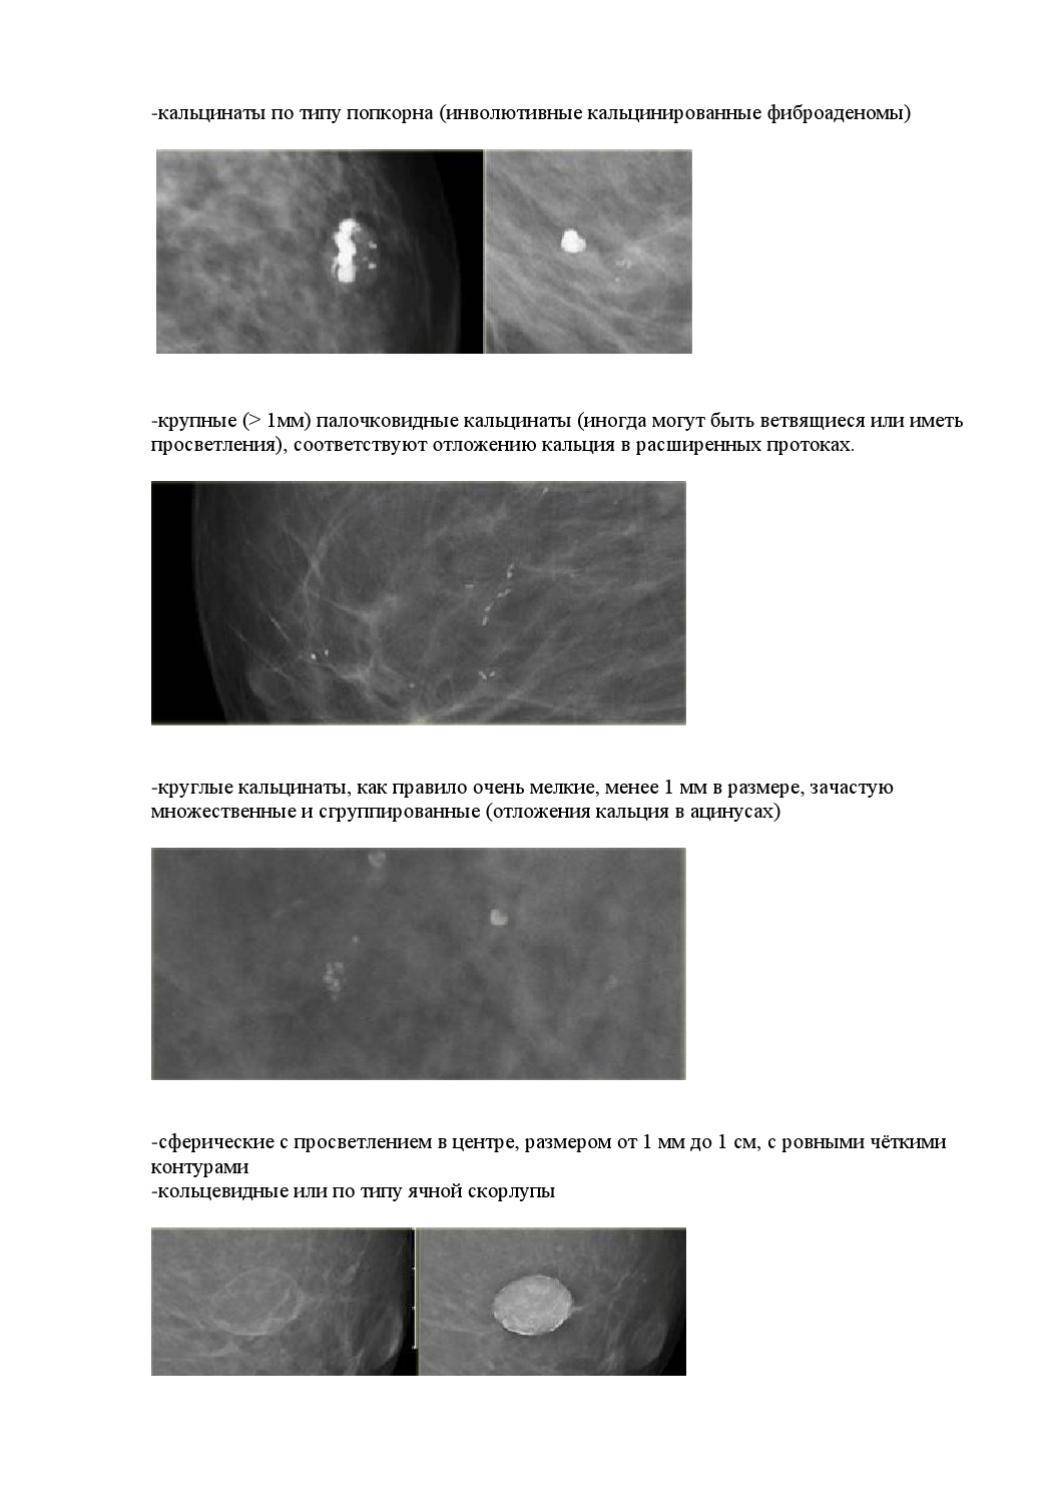

Маммограмма кальцинаты визуализируются

Кальцинаты маммограмма